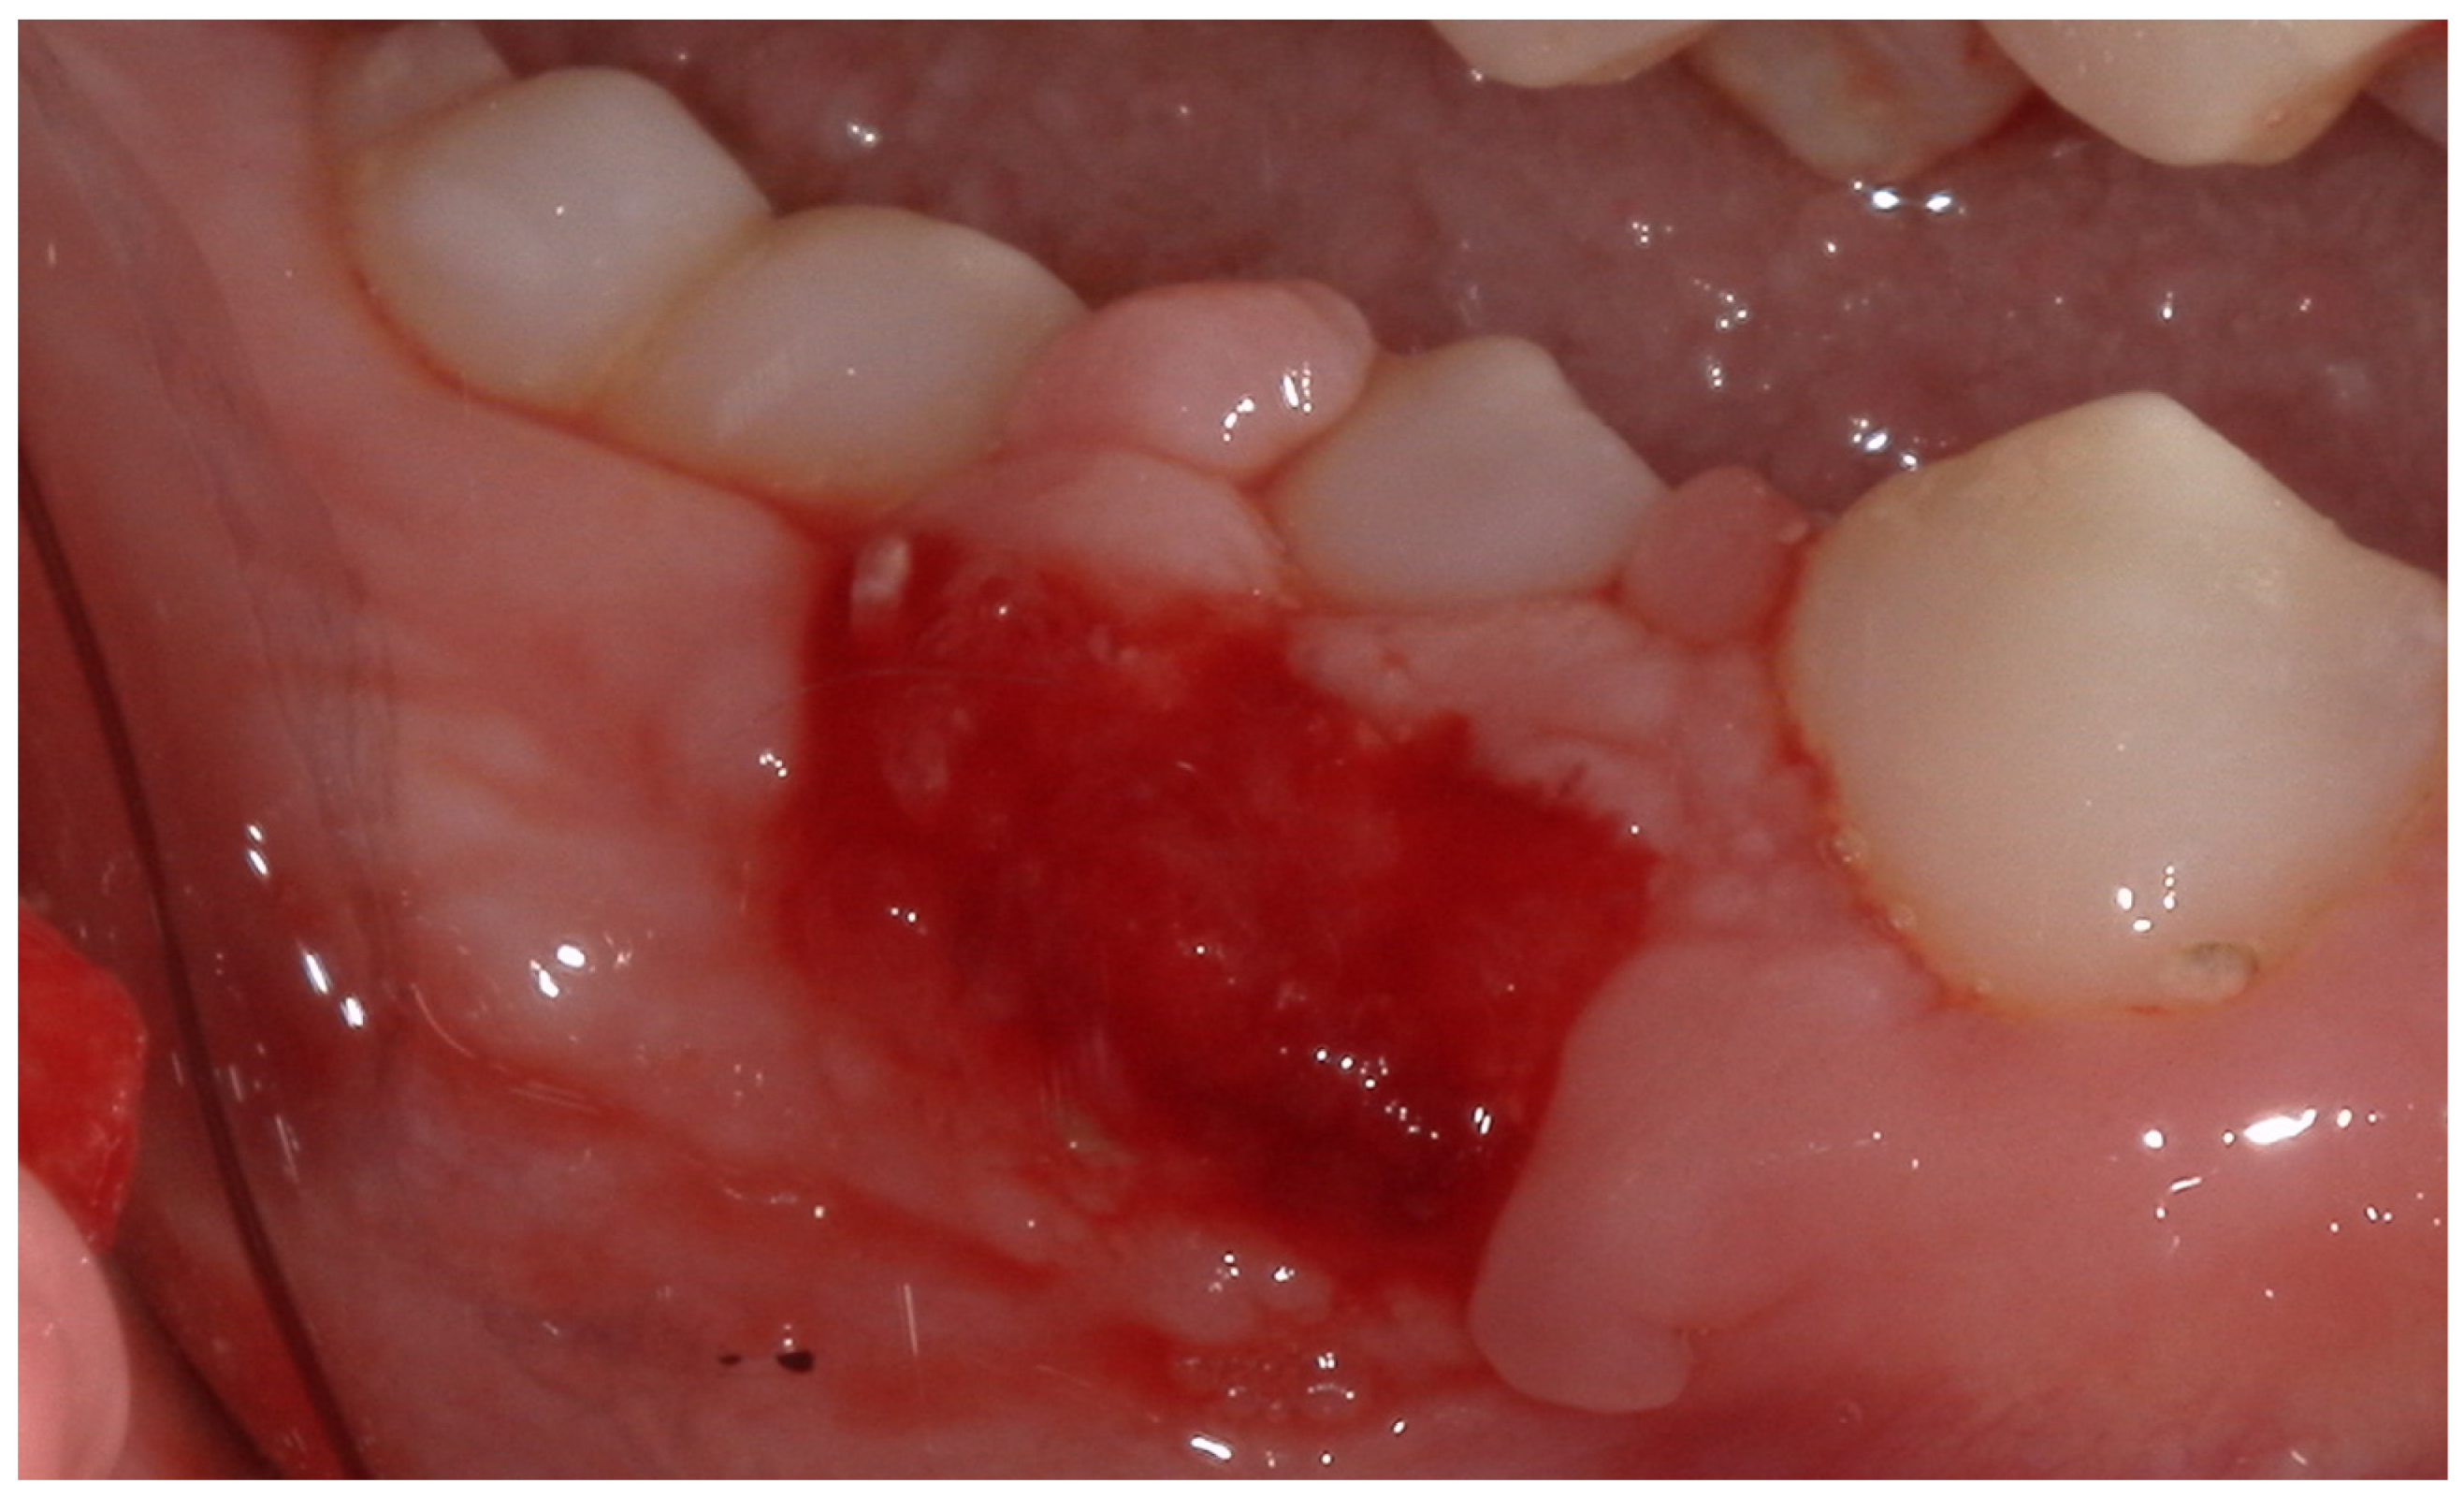

2.4. Therapeutic Intervention

2.5. Follow-Up and Outcomes